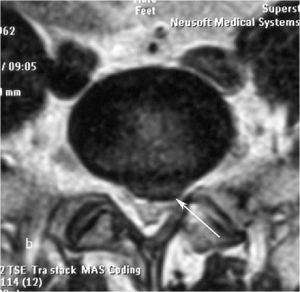

При рентгенографии (Рис.7) и МРТ (Рис.8) поясничного отдела позвоночника выявляется дегенеративный ретролистез L5 позвонка, секвестрированная парамедианная грыжа мп диска L5-S1 слева.

|

| Рис. 7а,b. Рентгенограмма поясничного отдела позвоночника в боковой (а) и прямой (b) проекциях до операции. Стрелкой показано смещение тела L5 позвонка кзади. | |